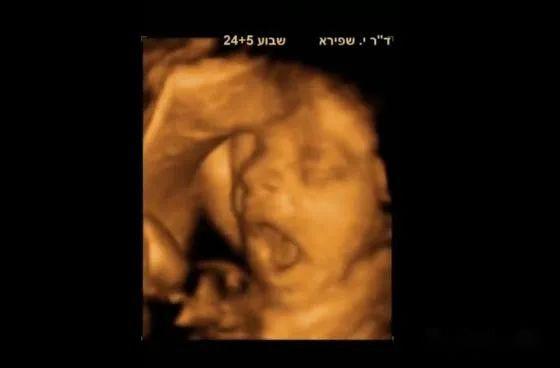

接下来我们一起去看看彩超筛查过程,胎宝宝一些神奇而调皮的举动: 打